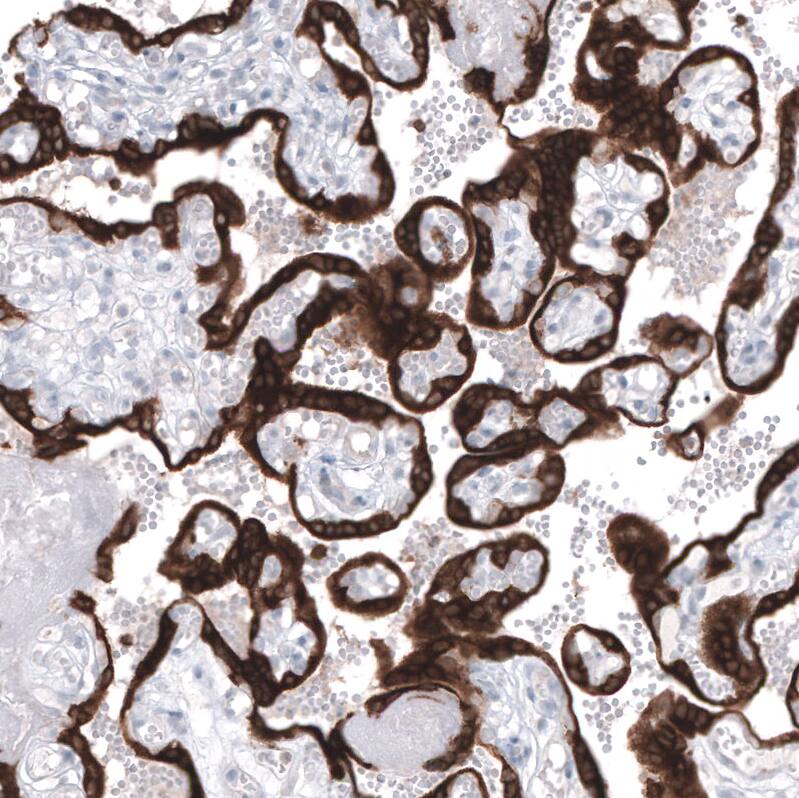

Staining of human placenta shows strong cytoplasmic positivity in trophoblastic cells.